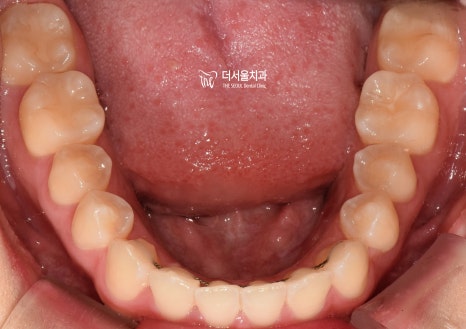

하악 앞니 뻗침은 생각보다 심하네요.

이런 문제들을 전체적으로 개선하기 위해서는

치아교정이 올바른 선택이란 생각이 들었습니다.